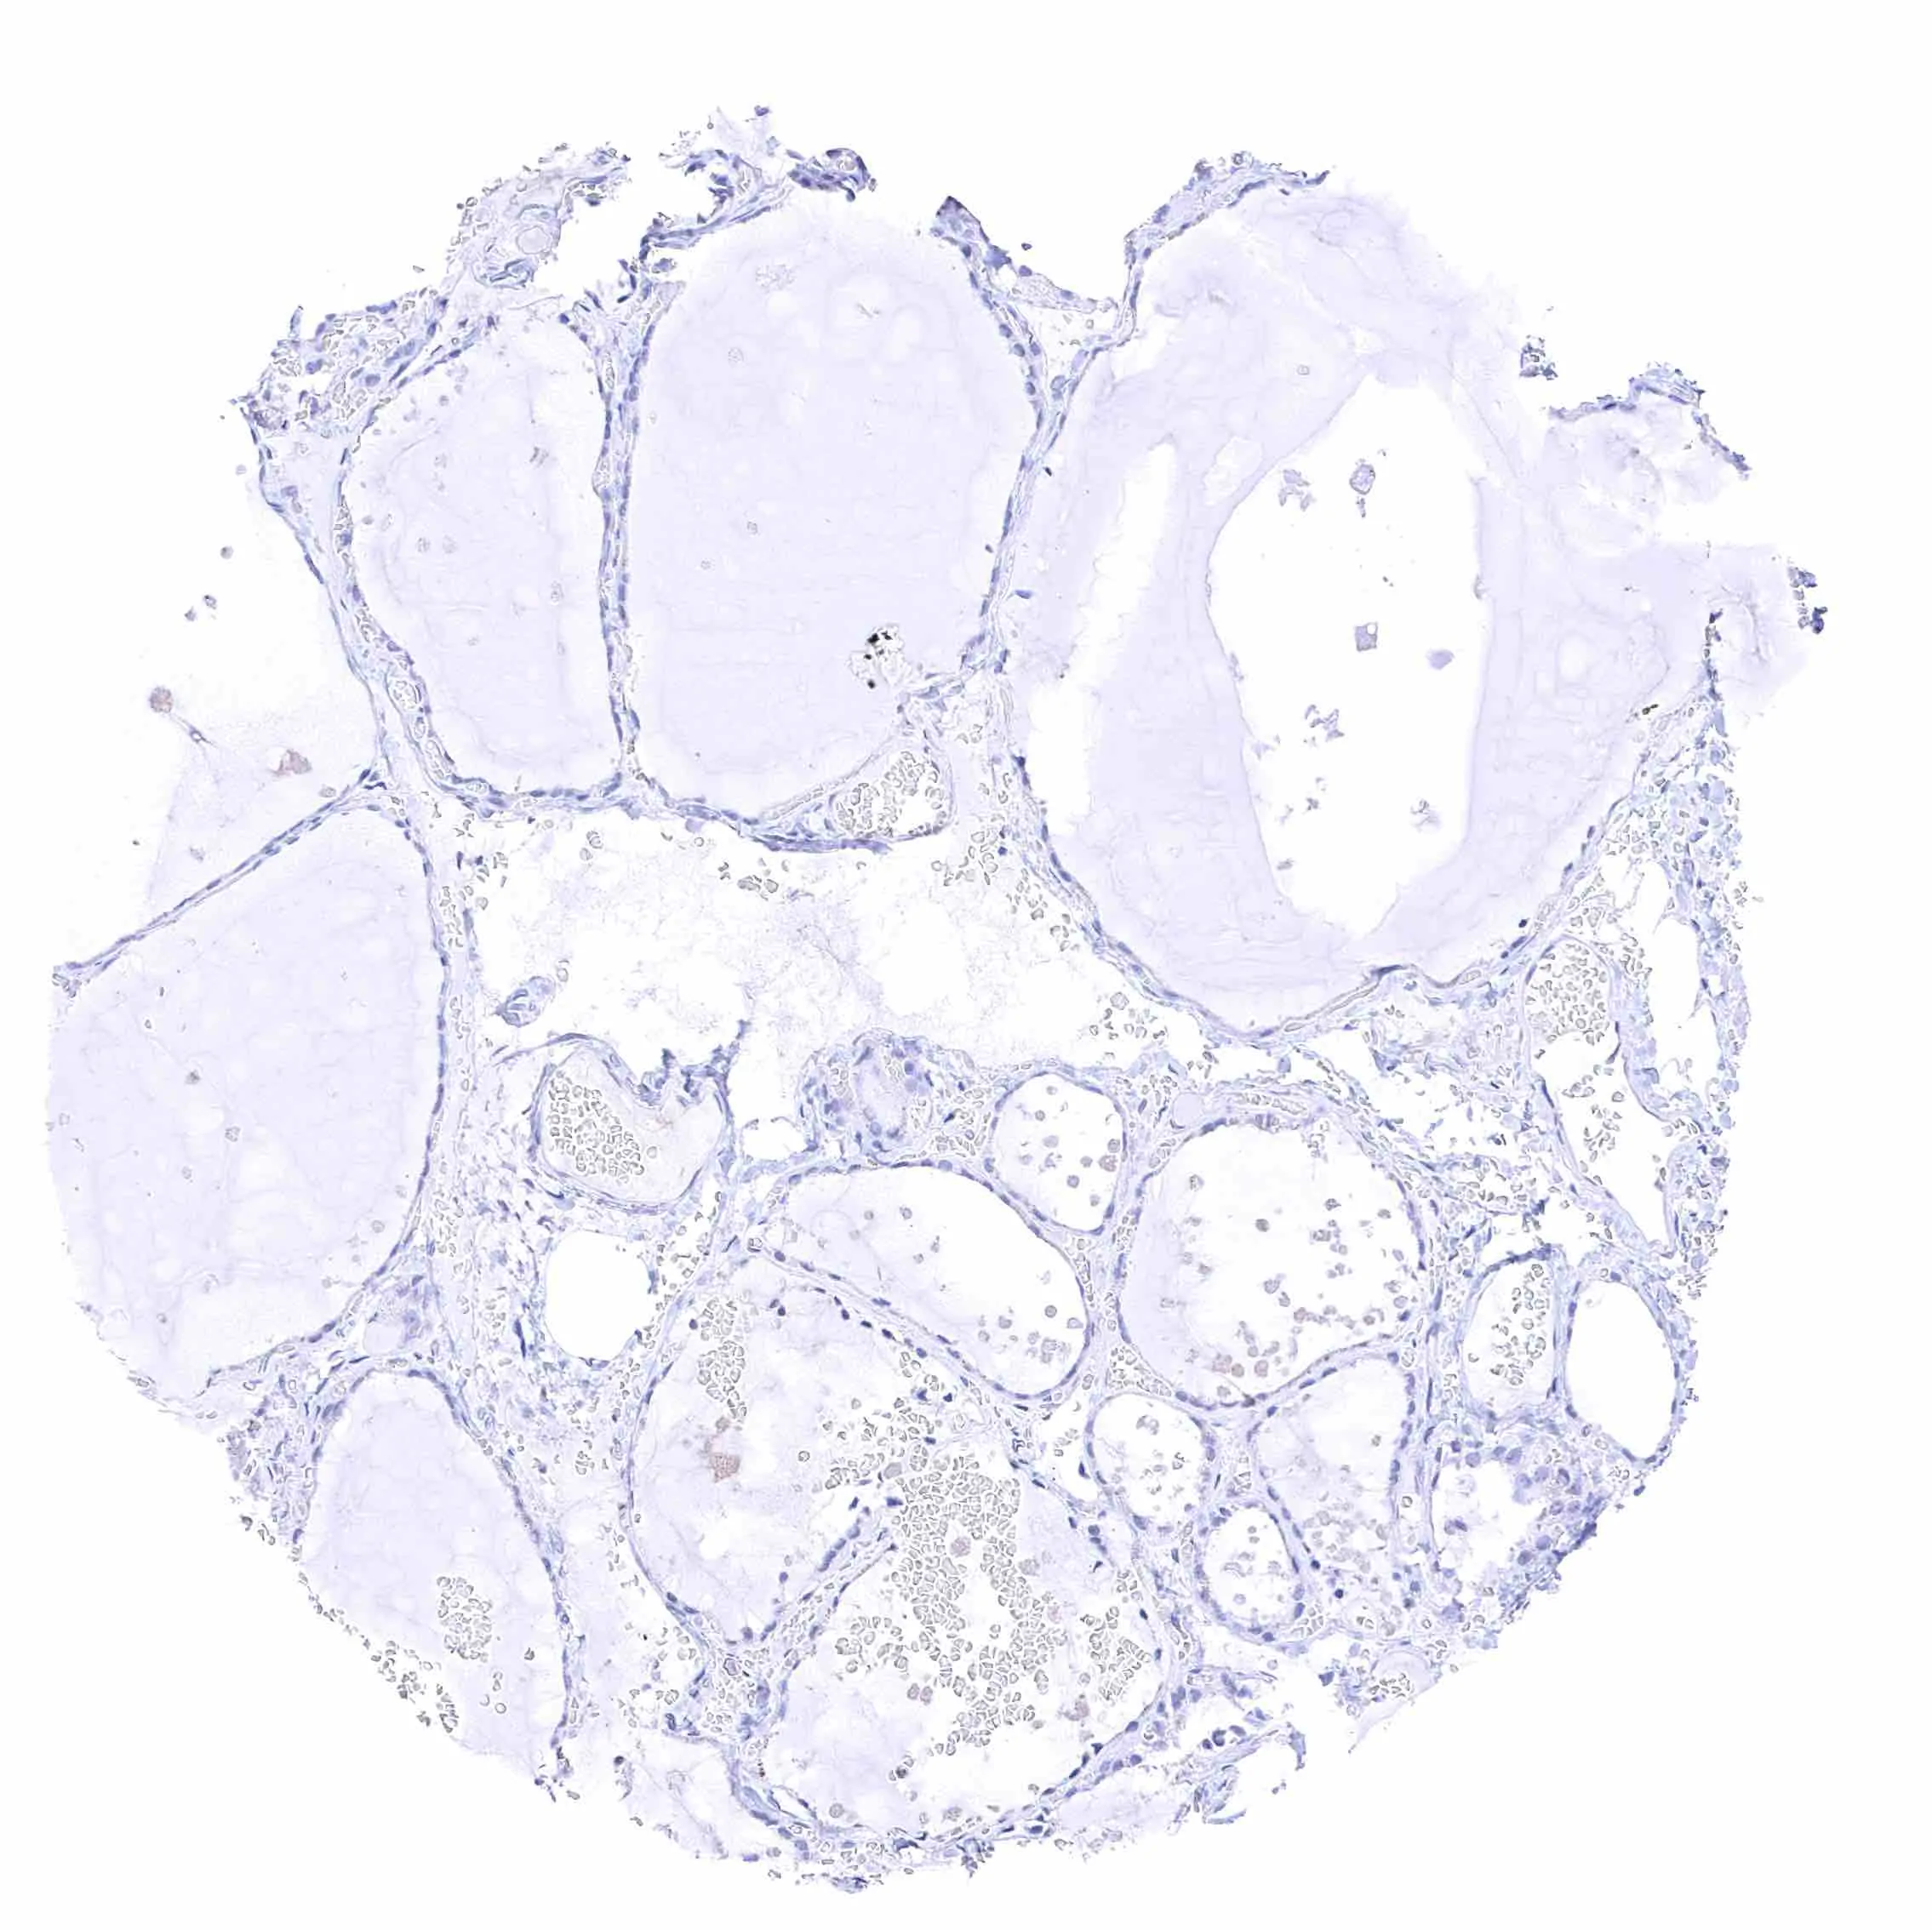

Ovary, follicular cyst – Strong membranous NPR-C staining of a subset of granulosa cells.

Ovary, stroma – Weak NPR-C staining of endothelial cells in one blood vessel but not in others.